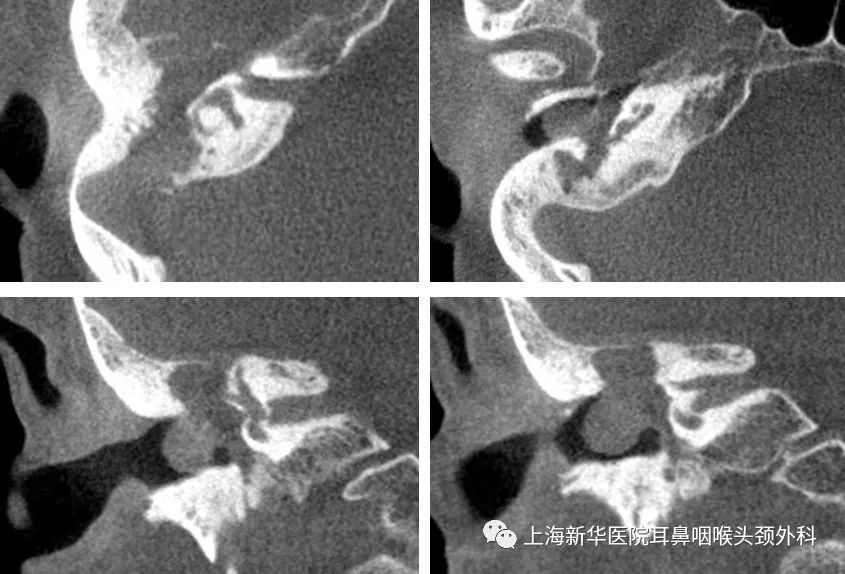

影像学检查:

术前MRI